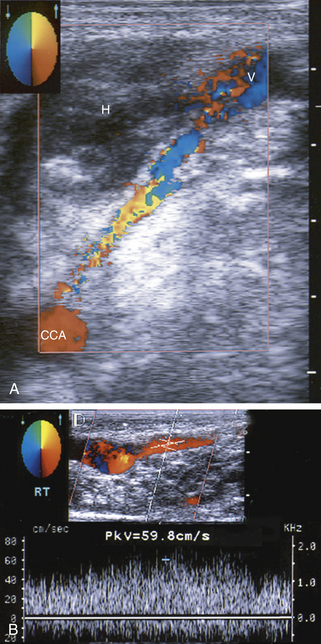

РИСУНОК 10-8. Каротидная артериовенозная фистула. А. На этом изображении в поперечном цветном потоке показан длинный тракт, соединяющий общую сонную артерию (ОСА) с поверхностной веной ( V ). Также видна гематома мягких тканей ( H ). Б. Допплерография дренирующей вены показывает турбулентный высокоскоростной поток (почти 60 см/сек).